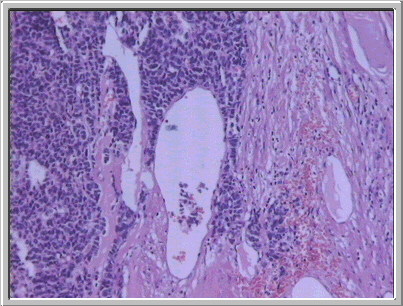

Fig. 6. En el tejido renal adyacente al tumor, algunas luces arteriolares muestran ocupación de su luz por células tumorales. (HE, X100.) |